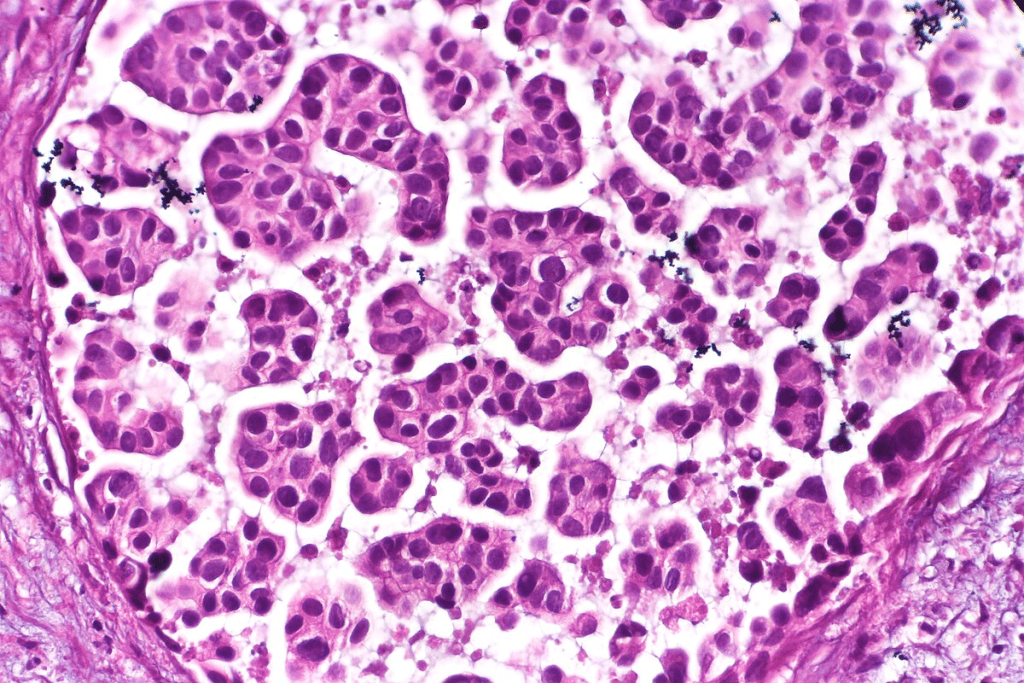

Bladder cancer is mainly classified into several types. The most common is urothelial carcinoma, or transitional cell carcinoma, making up about 90% of cases. Other types include squamous cell carcinoma and adenocarcinoma. Knowing the type is important for choosing the right treatment.